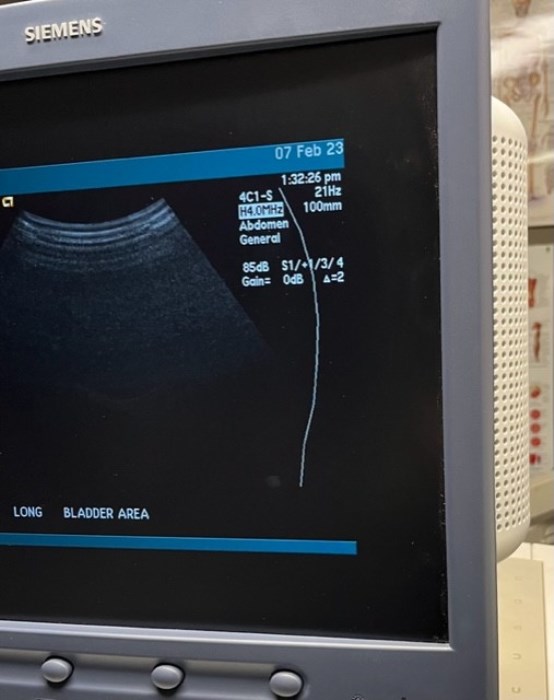

Siemens Sequioa Ultrasound

Pre-owned. In good working condition. Shown as is. Siemens Sequoia Ultrasound. DOM: 2006

Probes: 15L8w, 4V1, 10V4, 6L3, 4C1